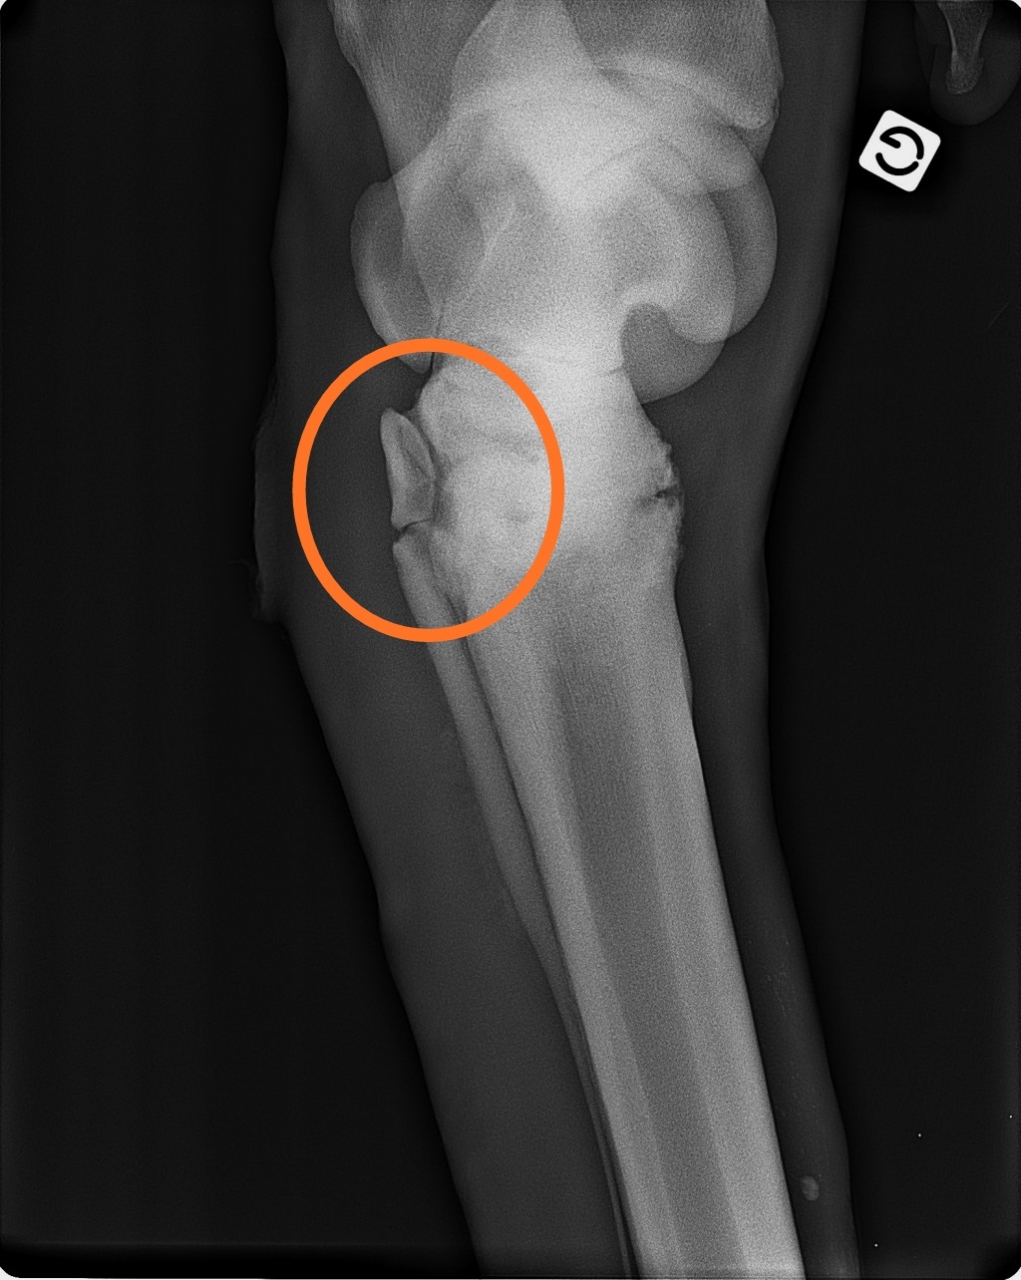

| Dire merci | mon cheval a une fracture de l'os rudimentaire médial À priori pas d'opération en vue, à confirmer dans les prochains jours Sinon traitement laser prévu J'attends la suite des directives de la véto A eu radios et écho samedi Transféré dans mon jardin, en van avec pont pour être au plat et en vue Faut que je prenne de la poudre calcique, et il a argile tous les jours Anti inflammatoire et antibiotiques 7 et 5j Il a 20ans ![]() ![]() ![]() Ce message a été modifié par un modérateur. |